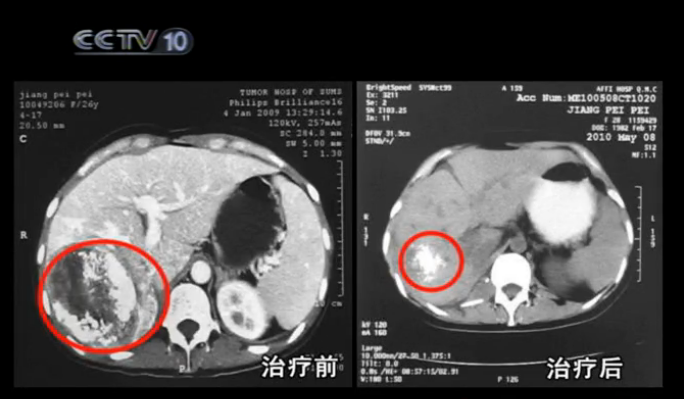

5¸öÔºó£¬Ð¡¼ÑÔÙ´ÎÀ´µ½307Ò½Ôº¸´²é£¬B³¬¼ì²éС¼Ñ¸ÎÇø¼°ÉöÇøÖ×Áöռλ¾ùÓÐËùËõС£¬³Â»¢Ö÷ÈÎʵʩµÄϸ°ûÃâÒßÖÎÁÆÆðµ½Á˺ܺõÄÁÆÐ§¡£

ÃâÒßϸ°ûûÓÐÈôó¼ÒʧÍû£¬Ëü¼ÌÐøÕ½¶·×Å£¬²»¶ÏÏûÃðÕßÌåÄڵݩϸ°û£¬2010Äê6Ô£¬°ëÄêºóµÄ¸´²éÏÔʾ£¬Ö׿éÒѾ­Ã÷ÏÔËõС£¬Ð¡¼ÑÖØÐ»À·¢×ÅÉú»ú£¬½ÓÏÂÀ´³Â»¢Ö÷ÈμÌÐø¸øÐ¡¼Ñ½øÐÐÖÎÁÆ£¬ËûÏ£ÍûÔÚС¼ÑÕâÀï¿´µ½ºÜ¶àµÄÆæ¼£·¢Éú¡£